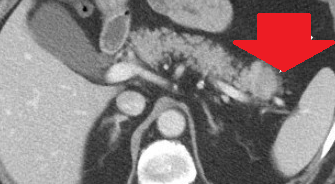

CT Angiography. Presence of a ruptured pseudoaneurysm of the common hepatic artery (Courtesy Dr. V. Penopoulos)